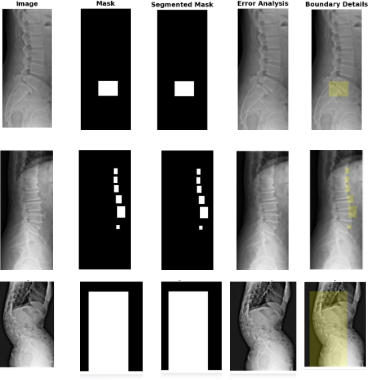

Qualitative Visualization

(c) Qualitative Visualization

Comparison of the ground truth mask and predicted mask along with error analysis for the DERNet model.

Why it's better: DERNet approach preserves local anatomical details often missed by Transformers.